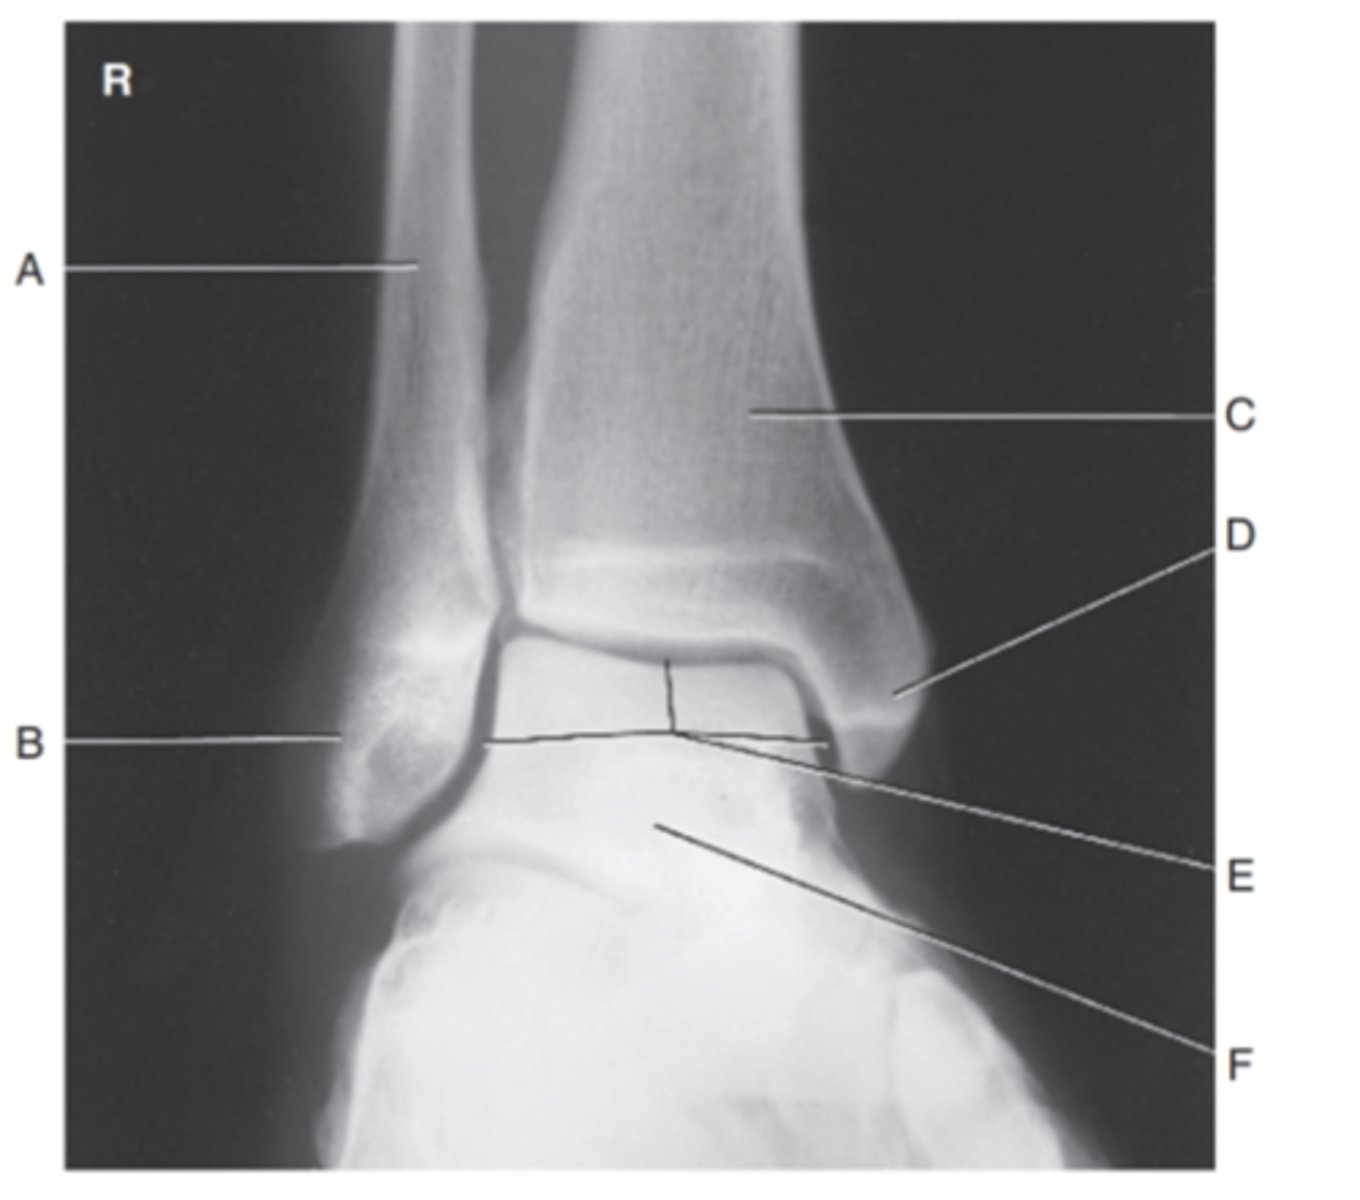

(MORTIS AP ANKLE) what is A?

fibula

what is B?

lateral malloelus

what is C?

tibia

what is D?

medial malleolus

what is E?

motrise joint

what is F?

talus